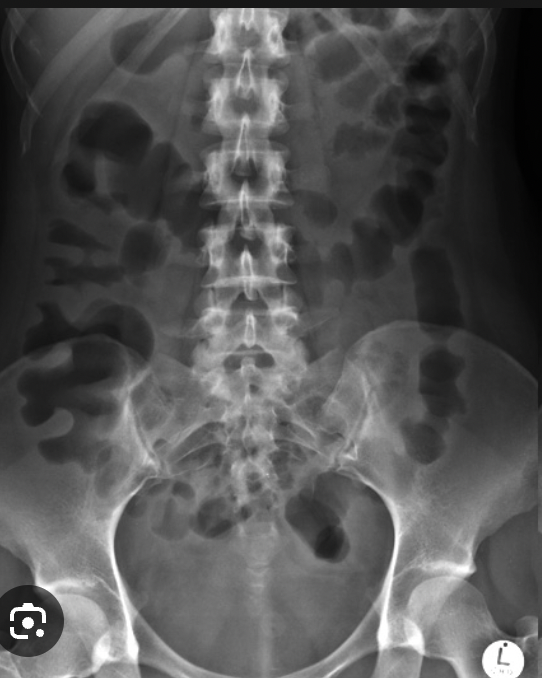

Cecal volvulus